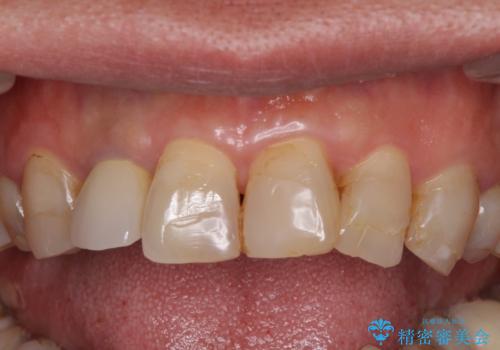

全体的に中等度の歯周病と診断されたため、歯周外科処置やインプラントによる咬合回復から進めて行き、矯正治療による歯列改善を行った後にオールセラミッククラウンにて補綴することとしました。

矯正治療を希望して来院されましたが、歯周病を併発していたため、矯正治療開始前の処置が非常に多くなりました。特に歯槽骨の再生治療を行ったため、外科処置後の静置期間が長くなり、4年弱の治療期間となりました。

治療後には咬みやすさだけでなく、前歯が大変審美的に仕上がり、患者様には大変満足していただきました。